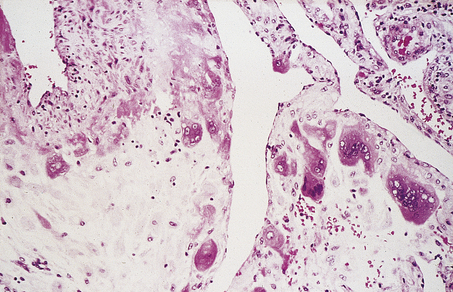

Genital warts or condylomata have been recognised for centuries. Only comparatively recently, however, has their viral aetiology been established. Electron microscopy showed the presence of viral particles, and immunohistochemistry (using antibodies to viral capsid antigen) and in situ hybridisation (using DNA probes) also confirmed their viral nature. Warts may affect the vulva but may also involve the cervix (Fig. 19.4). Moreover, it is now appreciated that human papillomaviruses (HPV) may infect the vulva, vagina and cervix in a non-condylomatous manner. Such infections show characteristic morphological features; most important of these is a specific cytoplasmic vacuolation called koilocytosis (Fig. 19.5). The features associated with human papillomavirus infection are:

image

Fig. 19.4 Florid condyloma of the cervix.